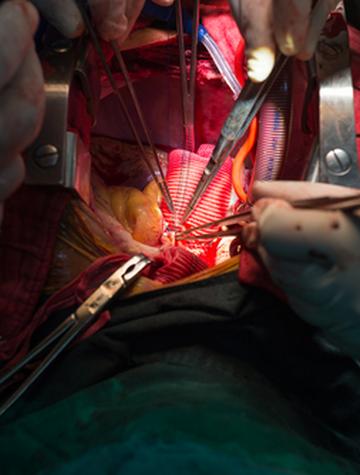

La sarcoïdose est une maladie multi-organique de cause inconnue caractérisée par une inflammation granulomateuse non nécrosante, touchant le plus souvent les poumons. La confirmation nécessite d’exclure d'autres affections, dont la bérylliose chronique qui ne peut être distinguée de la sarcoïdose sans tests spécifiques. Si la bérylliose chronique se développe principalement après inhalation de béryllium, la sensibilisation cutanée constitue un risque, et surtout, une [...]